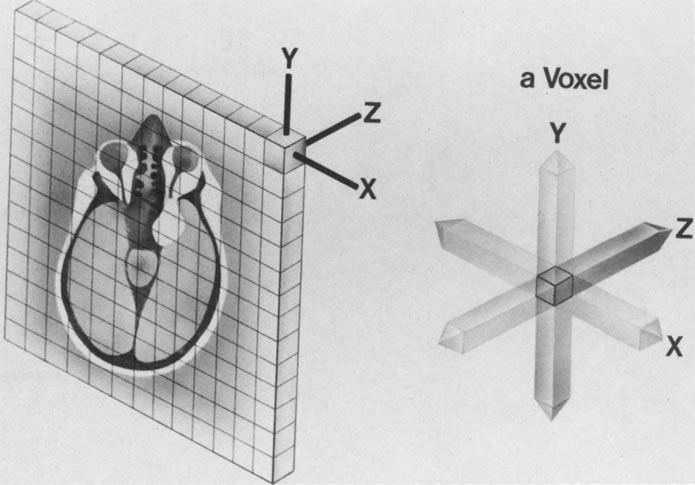

GRADIENT COILS

The spatial encoding information required for imaging the MR signal is achieved by use of gradient coils. These coils surround the patient's body in the MRI unit and select the plane (axial, coronal, sagittal, or oblique) to be studied (Fig. 6). A gradient magnetic field is applied by these coils perpendicular to the specified tissue section and isolates the desired plane's RF signal. These signals are further localized by additional manipulation of the magnetic fields parallel to the tissue section into multiple-volume units called voxels (Fig. 7). Each voxel represents a group of hydrogen nuclei with a unique sum of frequencies and phases. A computer reconstructs the signals from these individual three-dimensional voxels into corresponding pixels that compose the two-dimensional image of that plane. The intensity, or whiteness, of each pixel is proportional to the strength of the RF energy obtained from the corresponding voxel.5,15

SPATIAL RESOLUTION

Spatial resolution in MRI refers to the discrimination between two points in the image and is dependent on the number and size of pixels; thus, a larger number of smaller pixels in a given field of view yields better spatial resolution. For examinations of the orbits that involve a relatively small area, the field of view can be diminished, thereby reducing the pixel size and improving spatial detail. A reduction of the slice thickness of the plane under study (represented by voxel volume) also improves anatomic delineation by limiting partial volume effects. However, a decrease in the field of view, pixel size, or slice thickness may also adversely affect image quality by causing a concomitant reduction in the signal-to-noise ratio (SNR). Therefore, a compromise of the appropriate parameters must be chosen by the MRI operator to achieve the best image quality for a particular area to be studied.5,15,16